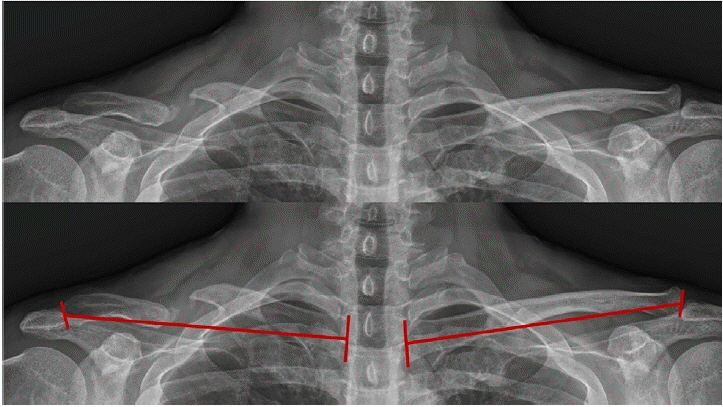

Radiological outcomes were assessed by serial plain radiographs to confirm bone union and clavicle length difference (CLD) after index surgery. Bony union was defined as a completely bridging bone in both anterosuperior and oblique views of clavicle. Using both anteroposterior clavicle plain radiograph, total length of the clavicle was measured bilaterally and defined as the linear distance between the midpoint of the acromial end and the midpoint of the sternal end of the clavicle (Fig. 2). Clinical outcomes were assessed using the University of California, Los Angeles (UCLA) score, American Shoulder and Elbow Surgeons (ASES) score, and Quick-disabilities of the arm, shoulder, and hand (DASH) score. Intraoperative and postoperative complications were also evaluated.

Fig. 2.

Preoperative radiographs of 48-year-old man (case no. 14) with right atrophic clavicle nonunion. The clavicle length (red line) was determined on standard anteroposterior plain radiograph by measuring the linear distance between the midpoint of the acromial end and the midpoint of the sternal end of the clavicle.